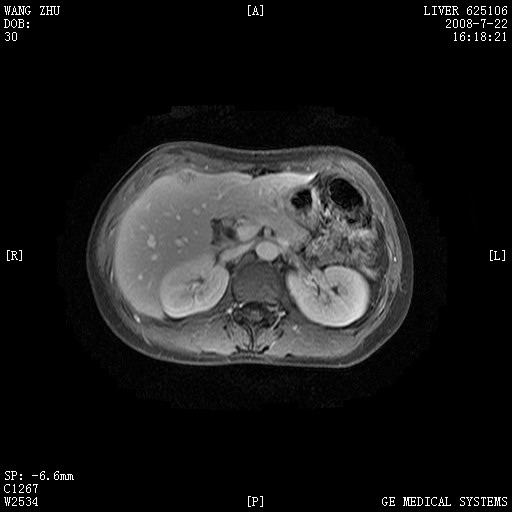

图像有点乱,病灶边缘清楚,可见纤维囊壁,灶旁可见异常灌注,增强显著增强,病灶有早期完全充填,无快退征像,考虑炎性病灶,肝结核可能性大,不知有何病史

肝前外缘见一类圆形囊性病灶,边缘强化,灶周肝为炎性渗出改变,其肝周可见少量腹水,符合炎性病变,病史较长---考虑腹膜结核。肝为外压性改变,脾为动脉期改变。